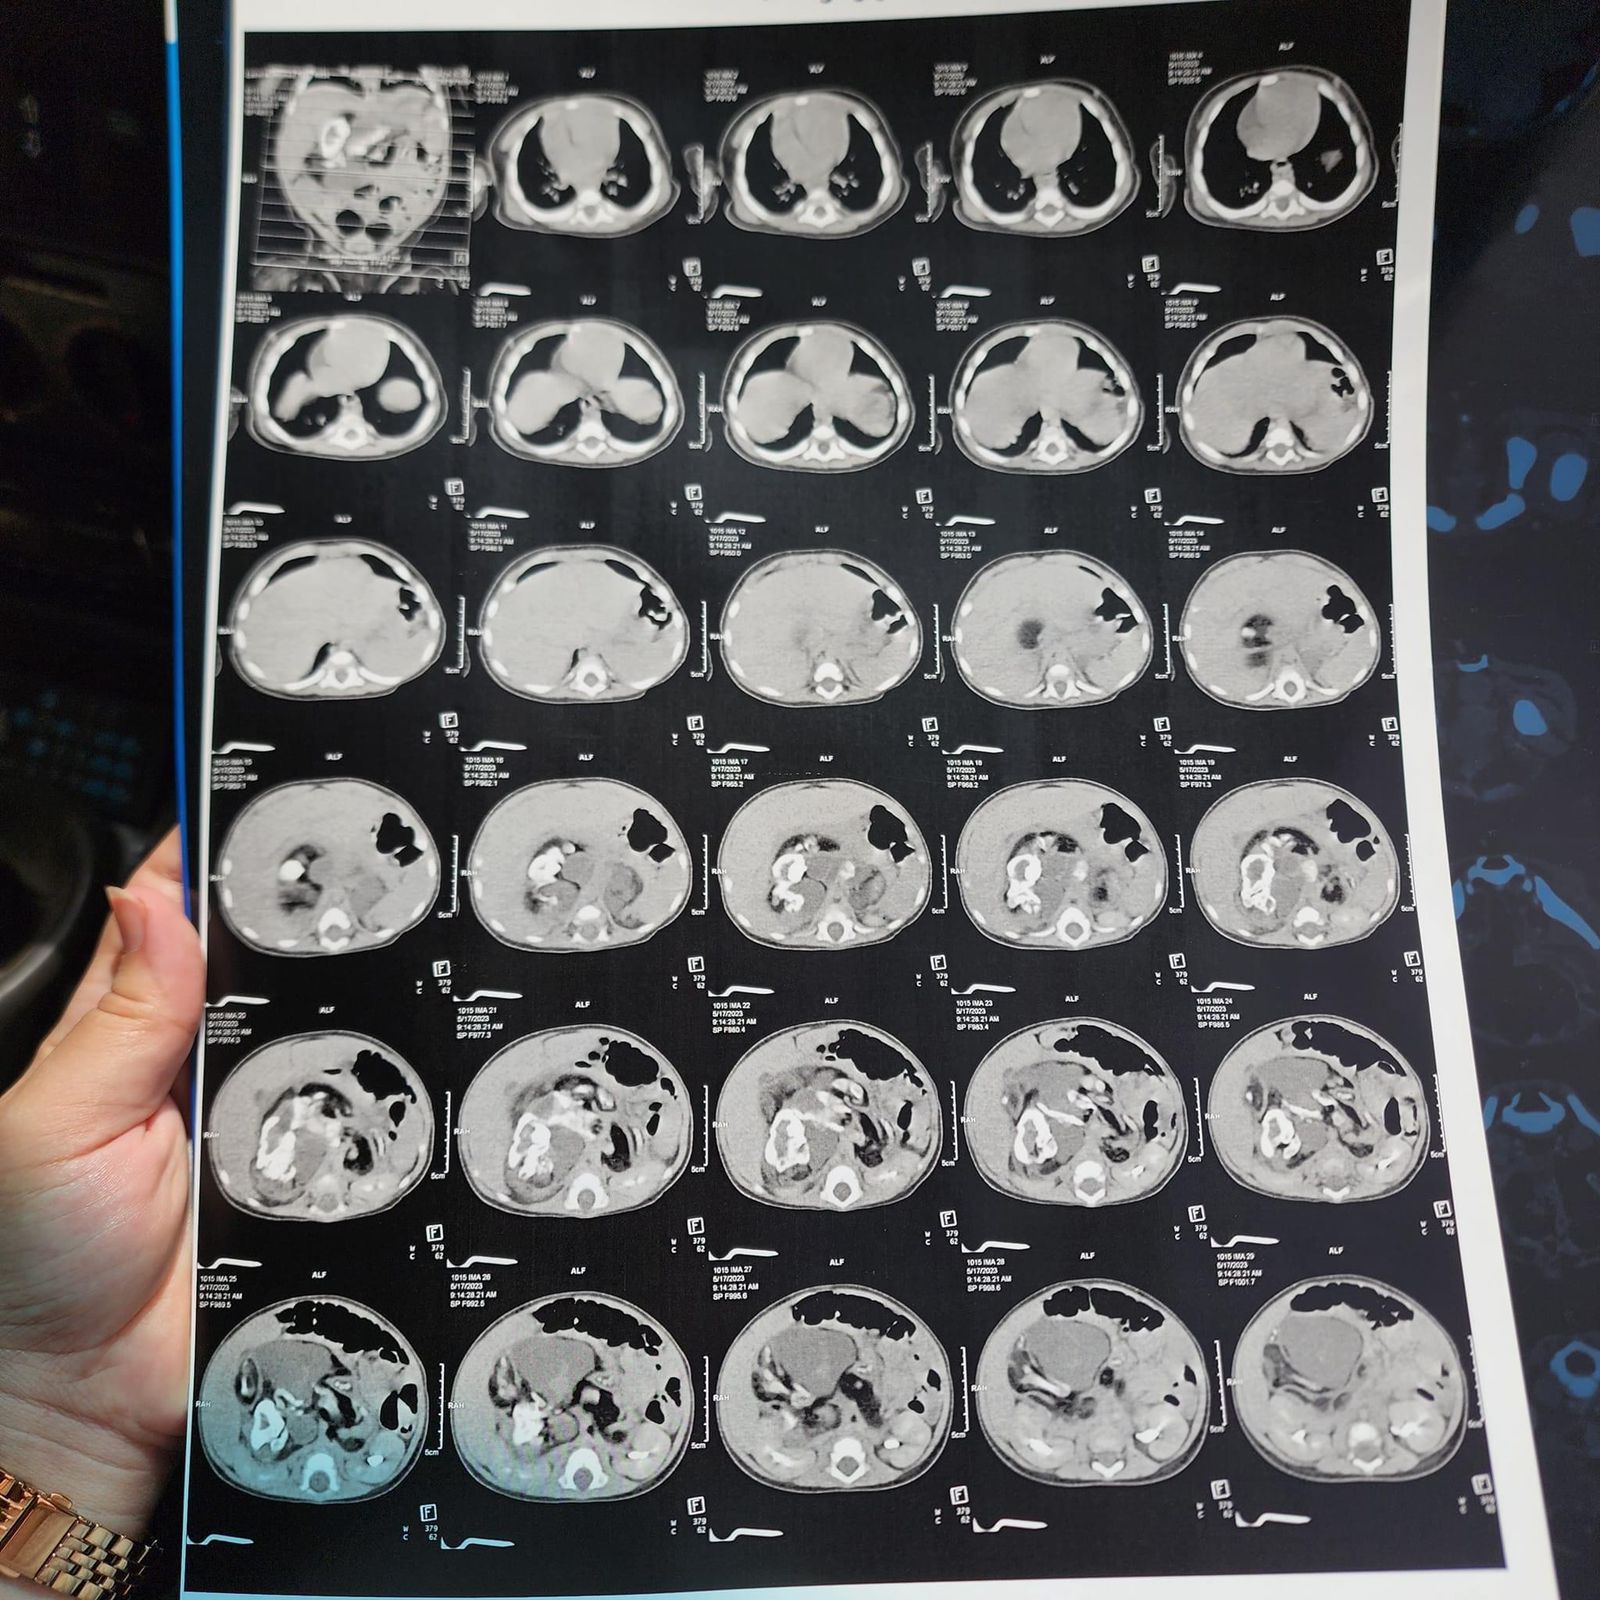

وأوضحت والدة الطفلة نورين، أنها اكتشفت الورم من خلال ظهور بعض الأعراض على الطفلة، ومنها التقيؤ المستمر، ومن خلال إجراء بعض الفحوصات الطبية، تبين أن الطفلة تعاني من ورم نادر في البطن بحجم 13 سم في الجانب الأيمن من الجسم بالكامل، بالإضافة إلى أنه ضاغط على الكلى والشريان الأورطي وباقي أجهزة الجهاز الهضمي.

وطالبت بتسريع دخول ابنتها مستشفى سرطان الأطفال، قائلة: الدكاترة شخصوا حالتها بورم سرطاني نادر، وهو حالة تراتوما، وضاغط على أجهزة الجسم غلط، احنا محتاجين تسريع موعد العملية لأن الورم بيكبر، ومع سن بنتي العملية صعبة وخطيرة.